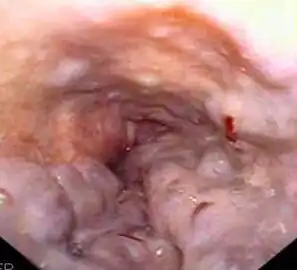

Гастроинтестинальная эндоскопия

Эндоскопические исследования выполняются с помощью специальных аппаратов-эндоскопов, вводимых пациенту через естественные отверстия — рот или задний проход и передающих изображение в исследуемом органе или на окуляр эндоскопа или на монитор. В современной практике используются два типа гибких эндоскопов: волоконно-оптические фиброэндоскопы и видеоэндоскопы, оцифровывающие видимую в объектив картинку и передающие её в таком виде на монитор или окуляр. Эзофаго-, гастро-, дуодено- и/или еюноскопия показаны при подозрении на воспаление или язву, а также другие заболевания пищевода, желудка, тонкой кишки, фатерова сосочка. Колоноскопия — эндоскопическое исследование толстой кишки, показана при наличии клинических признаков, указывающих на поражение толстой кишки, наблюдении за пациентом в процессе лечения, при осмотрах, направленных на выявление на ранней стадии онкологических и других заболеваний[22].

Полипы фундальных желёз желудка. Изображение получено с помощью фиброгастроскопа